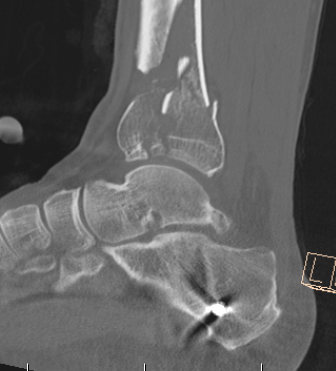

CT scan

Commonly 3 fracture configurations

- medial malleolus

- posterolateral fragment / Volkmann

- anterolateral fragment / Chaput